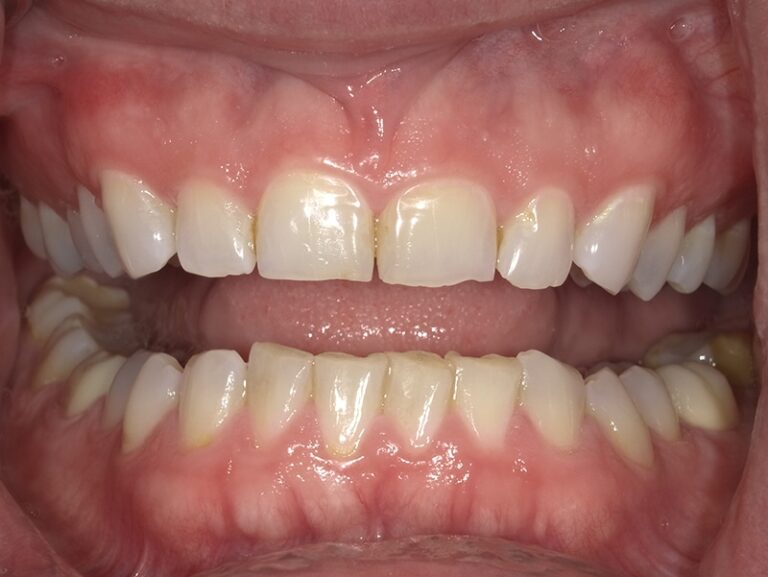

We began this patient's cosmetic journey with SureSmile clear aligners. We were able to accommodate patient's request of a shorter aligner treatment length, and move on to porcelain restorations. We placed 12 upper crowns and 6 lower veneers, thus giving her a beautiful new smile in a shorter timeframe!